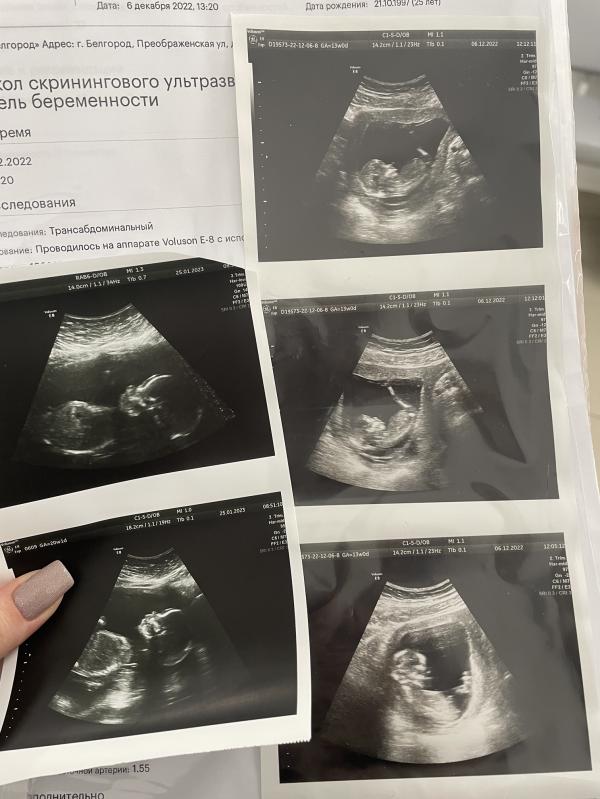

Я же была 25 числа на втором скрининге) сравнила фотки с первого и со второго

Такая большая мадам у нас уже)

Развиваемся по сроку (ну на 2 дня больше срок по узи, я это не считаю), предполагаемый вес 357 грамм 💖

3D хотел врач попробовать, но часть лица закрыта плацентой. Хотя я рассмотрела губки и носик 🥰 А вообще, малышка отвернулась спиной, не давала нормально посмотреть сердечко. Но мы ее обманули) я встала, походила, она решила, что от нее отстали, и повернулась - успели все рассмотреть.